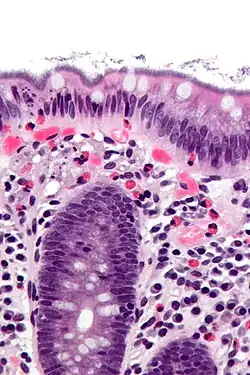

Histopathology of intestinal spirochetosis, showing basophilic, fringe-like, end-on-end attachment of filamentous densely packed spirochetes on the surface epithelium of the intestinal mucosa.[1] H&E stain.

Micrograph showing intestinal spirochetosis. H&E stain.

It is diagnosed by examination of tissue, i.e., biopsy. A hallmark finding is the presence of a “false brush border” on the luminal surface of the epithelium, formed by dense linear colonization of spirochetes.[4]